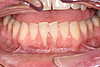

L'aménagement des tissus gingivaux dans le cadre des traitements implantaires

Un implant est envisagé pour remplacer une incisive perdue, mais le volume de gencive résiduelle est trop faible.

Une greffe de gencive concomitante à la pose de l'implant permet de retrouver un volume de gencive adéquat.